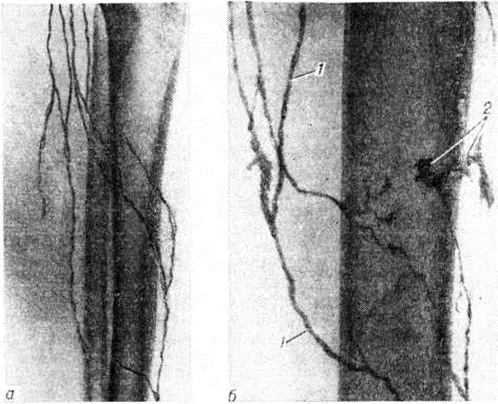

Особенностью лимфографии при поверхностной Лимфангиэктазия является возможность выполнять исследование путём чрескожной пункции расширенного лимфатических, сосуда. Вследствие повышенного лимфатических, давления контрастное вещество локализуется преимущественно в дистальных отделах поражённой области, выявляя расширенные лимфатических, сосуды и увеличенное их количество (рисунок).

Рис

Лимфограммы: а — лимфограмма голени в норме; 6 — лимфограмма бедра через месяц после термического ожога III степени (1 —расширенные лимфатические сосуды, 2 — обрывы лимфатических сосудов с выходом контрастного вещества в мягкие ткани).